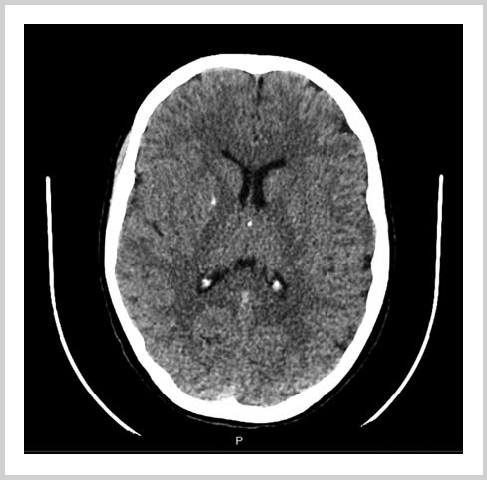

Помимо подкожных кальцинатов, при ПГП могут встречаться кальцинаты в ткани головного мозга (синдром Фара) (рис. 12) и в хрусталике (катаракта). Это не является характерным признаком именно ПГП, а лишь осложнением гипокальциемии и гиперфосфатемии и встречается при других болезнях, сопровождающихся низким содержанием кальция в крови и высоким содержанием фосфора (гипопаратиреоз, хроническая почечная недостаточность). Интересно, что среди наших пациентов осложнения, отражающие, как считается, большую длительность нарушений кальций-фосфорного обмена, в 60% случаев были выявлены при первичном обследовании, проведенном при манифестации проявлений гипокальциемии (первый эпизод судорог и/или синкопального состояния); самому младшему пациенту было 4,7 года. Это может объясняться тем, что возраст начала клинических проявлений гипокальциемии не совпадает с началом выявления снижения концентрации кальция в крови и повышением содержания фосфора. Обращает на себя внимание и разница в концентрации кальция в крови у 8 пациентов с синдромом Фара и длительностью гипокальцемических судорог менее 1 года 0,6 (0,56; 0,66 ммоль/л и у 5 пациентов, страдавших от судорожного эпизода более 1 года прежде чем была выявлена гипокальциемия — 0,77 (0,67; 0,8 ммоль/л). Однако утверждать статистическую значимость такой разницы преждевременно из-за недостаточного размера выборки. Вопрос о длительности некупируемых изменений концентрации кальция и фосфора, достаточной для развития осложнений, остается открытым. Следует подчеркнуть, что кальцинаты головного мозга — самые частые осложнения гипокальцемии, и в нашем исследовании все случаи катаракты и гипоплазии эмали сопровождались синдромом Фара.

Рис. 12. Синдром Фара — кальцинаты в ткани головного мозга.